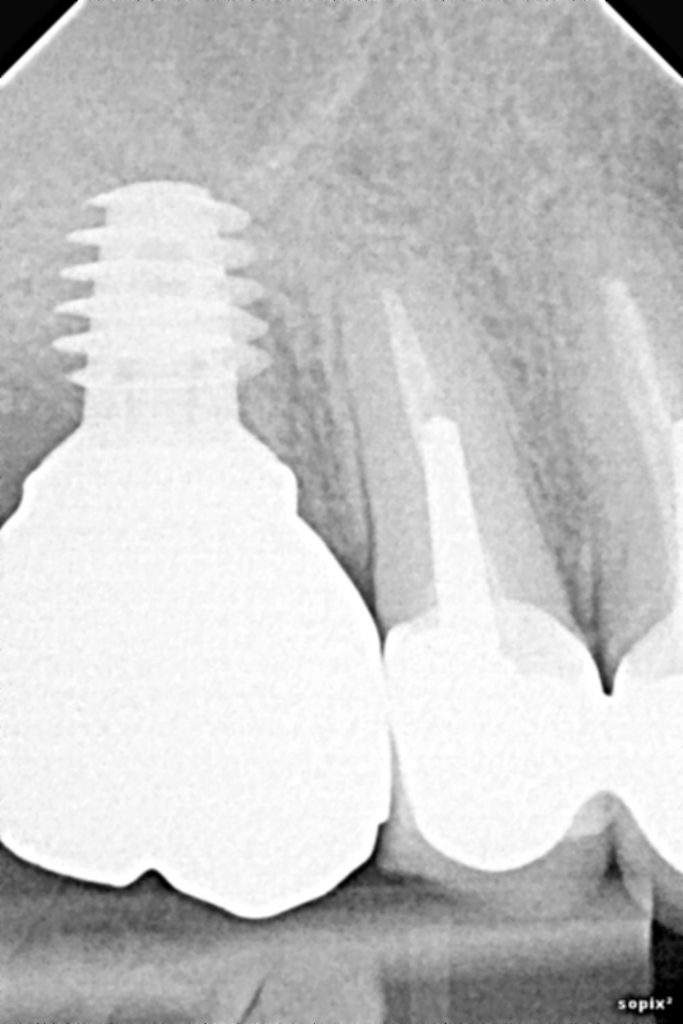

URB outils d'implant de règle d'angle dentaire Guide d'implant dentaire en acier inoxydable en. J'ai mes règles depuis plus d'un mois, sachant que je n'ai jamais pris la pilule de ma vie, que d'habitude mes règles durent 3-4 jours maximum Dans cet article, nous allons explorer l'impact de l'implant contraceptif.